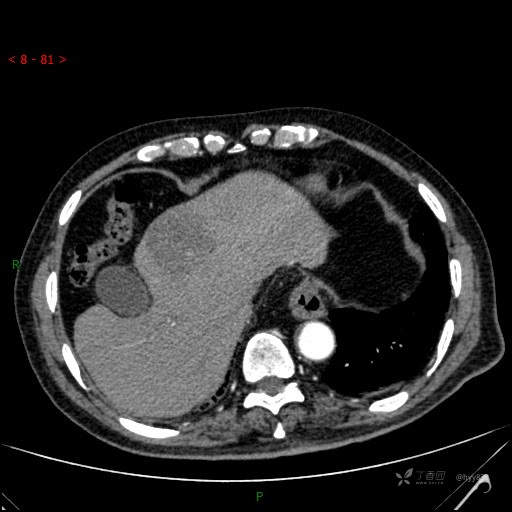

静脉期

img

肝脓肿 (73)